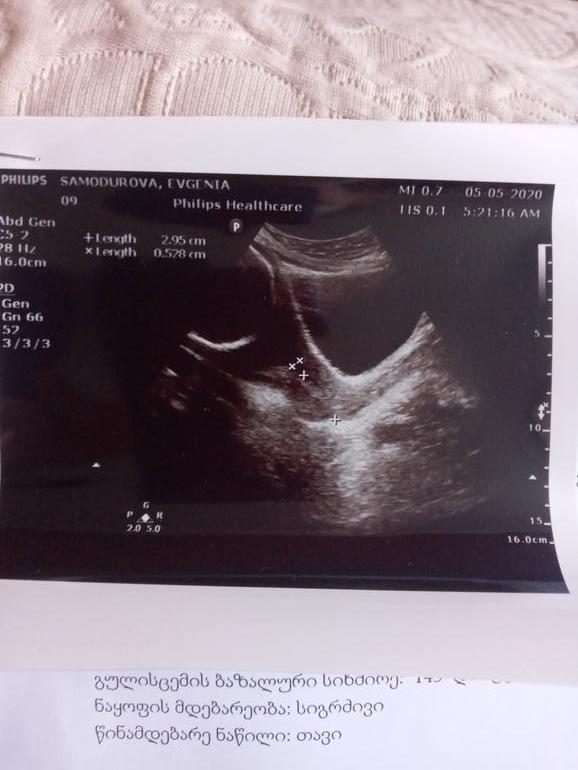

Здравствуйте девочки была на УЗИ там сказали что шейка укоротилась 29 мм внутренний зев приоткрыт 2мм сказали вставлять свечи индометацин и через 10 дней на контроль, я стараюсь лежать но периодически встаю покушать и в туалет, Скажите пожалуйста у кого такая ситуация была? это очень опасно?

Пока не знаю завтра будем на узи перепроверять, симптом никаких не было мы поехали в клинику с подозрением на подтекание вод , врачи опровергли наши апасание , только шейку короткую номерили , сказали может быть, это всё из-за гипертонуса. Сказали песарий ставить будут если не удлинится шейка